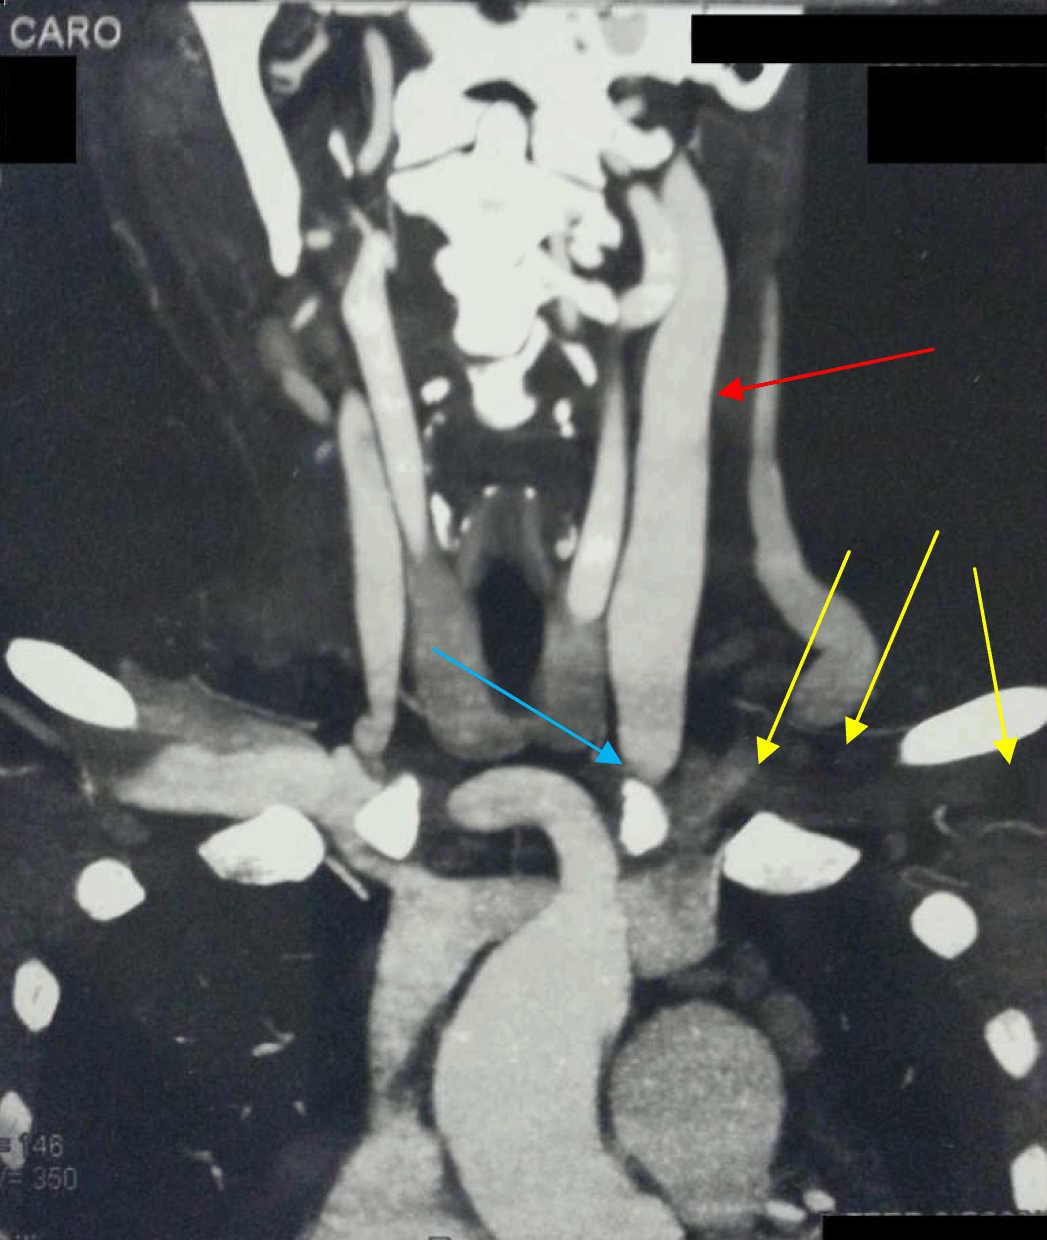

With the source of infection being the mycotic AVF pseudoaneurysm, the initial step of management included aneurysmectomy and AVF ligation to control the systemic infection. Postoperatively intravenous antibiotics and analgesia were administered. The fever subsequently subsided. Next, computed tomography angiogram of the head and neck showed a long segment occlusion on the left internal jugular vein extending to left brachiocephalic and subclavian veins (Figure 4) and evidence of a cavernous sinus thrombus (Figure 5); a diagnosis of a septic cavernous sinus thrombosis was made. The treatment included anticoagulant therapy, IV 3rd generation cephalosporin and periorbital eye dressing with honey and water. After the periorbital swelling and local infection subsided, she was discharged on oral anticoagulant therapy and daily eye dressing. She was later booked for debridement of a necrotic skin infection just below the right eye (Figure 6). After complete resolution of her condition, she now presents with ectropion of the right lower eye lid.

Figure 4: Subclavian and brachiocephalic vein thrombosis (yellow arrows), left internal jugular vein distension (red arrow), thrombosis (blue arrow).